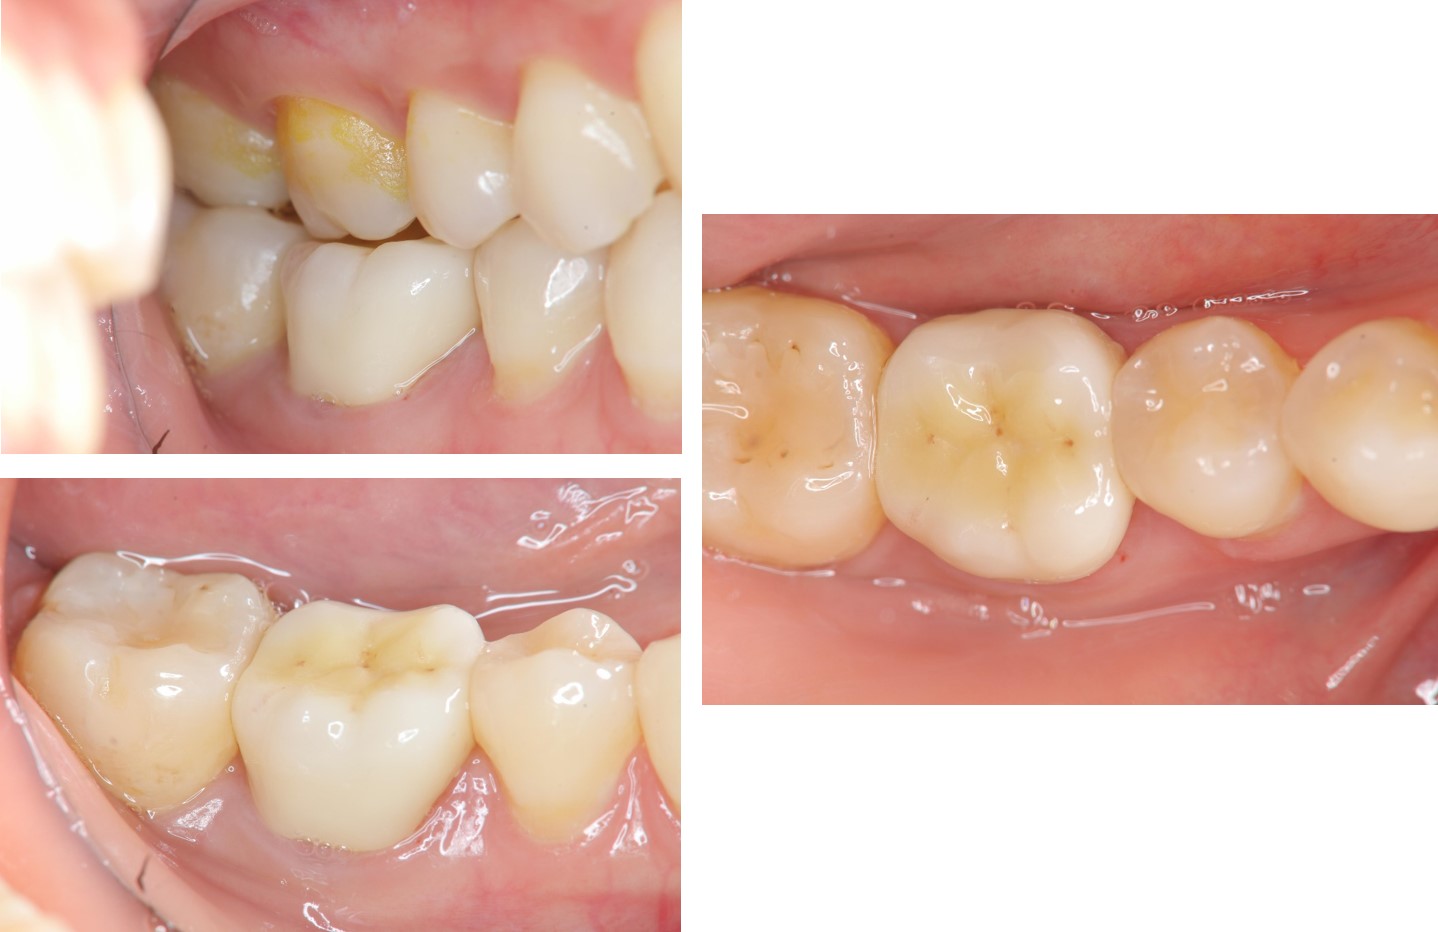

治療後,牙周咬合良好

治療後,密合度良好

術前、術後比較